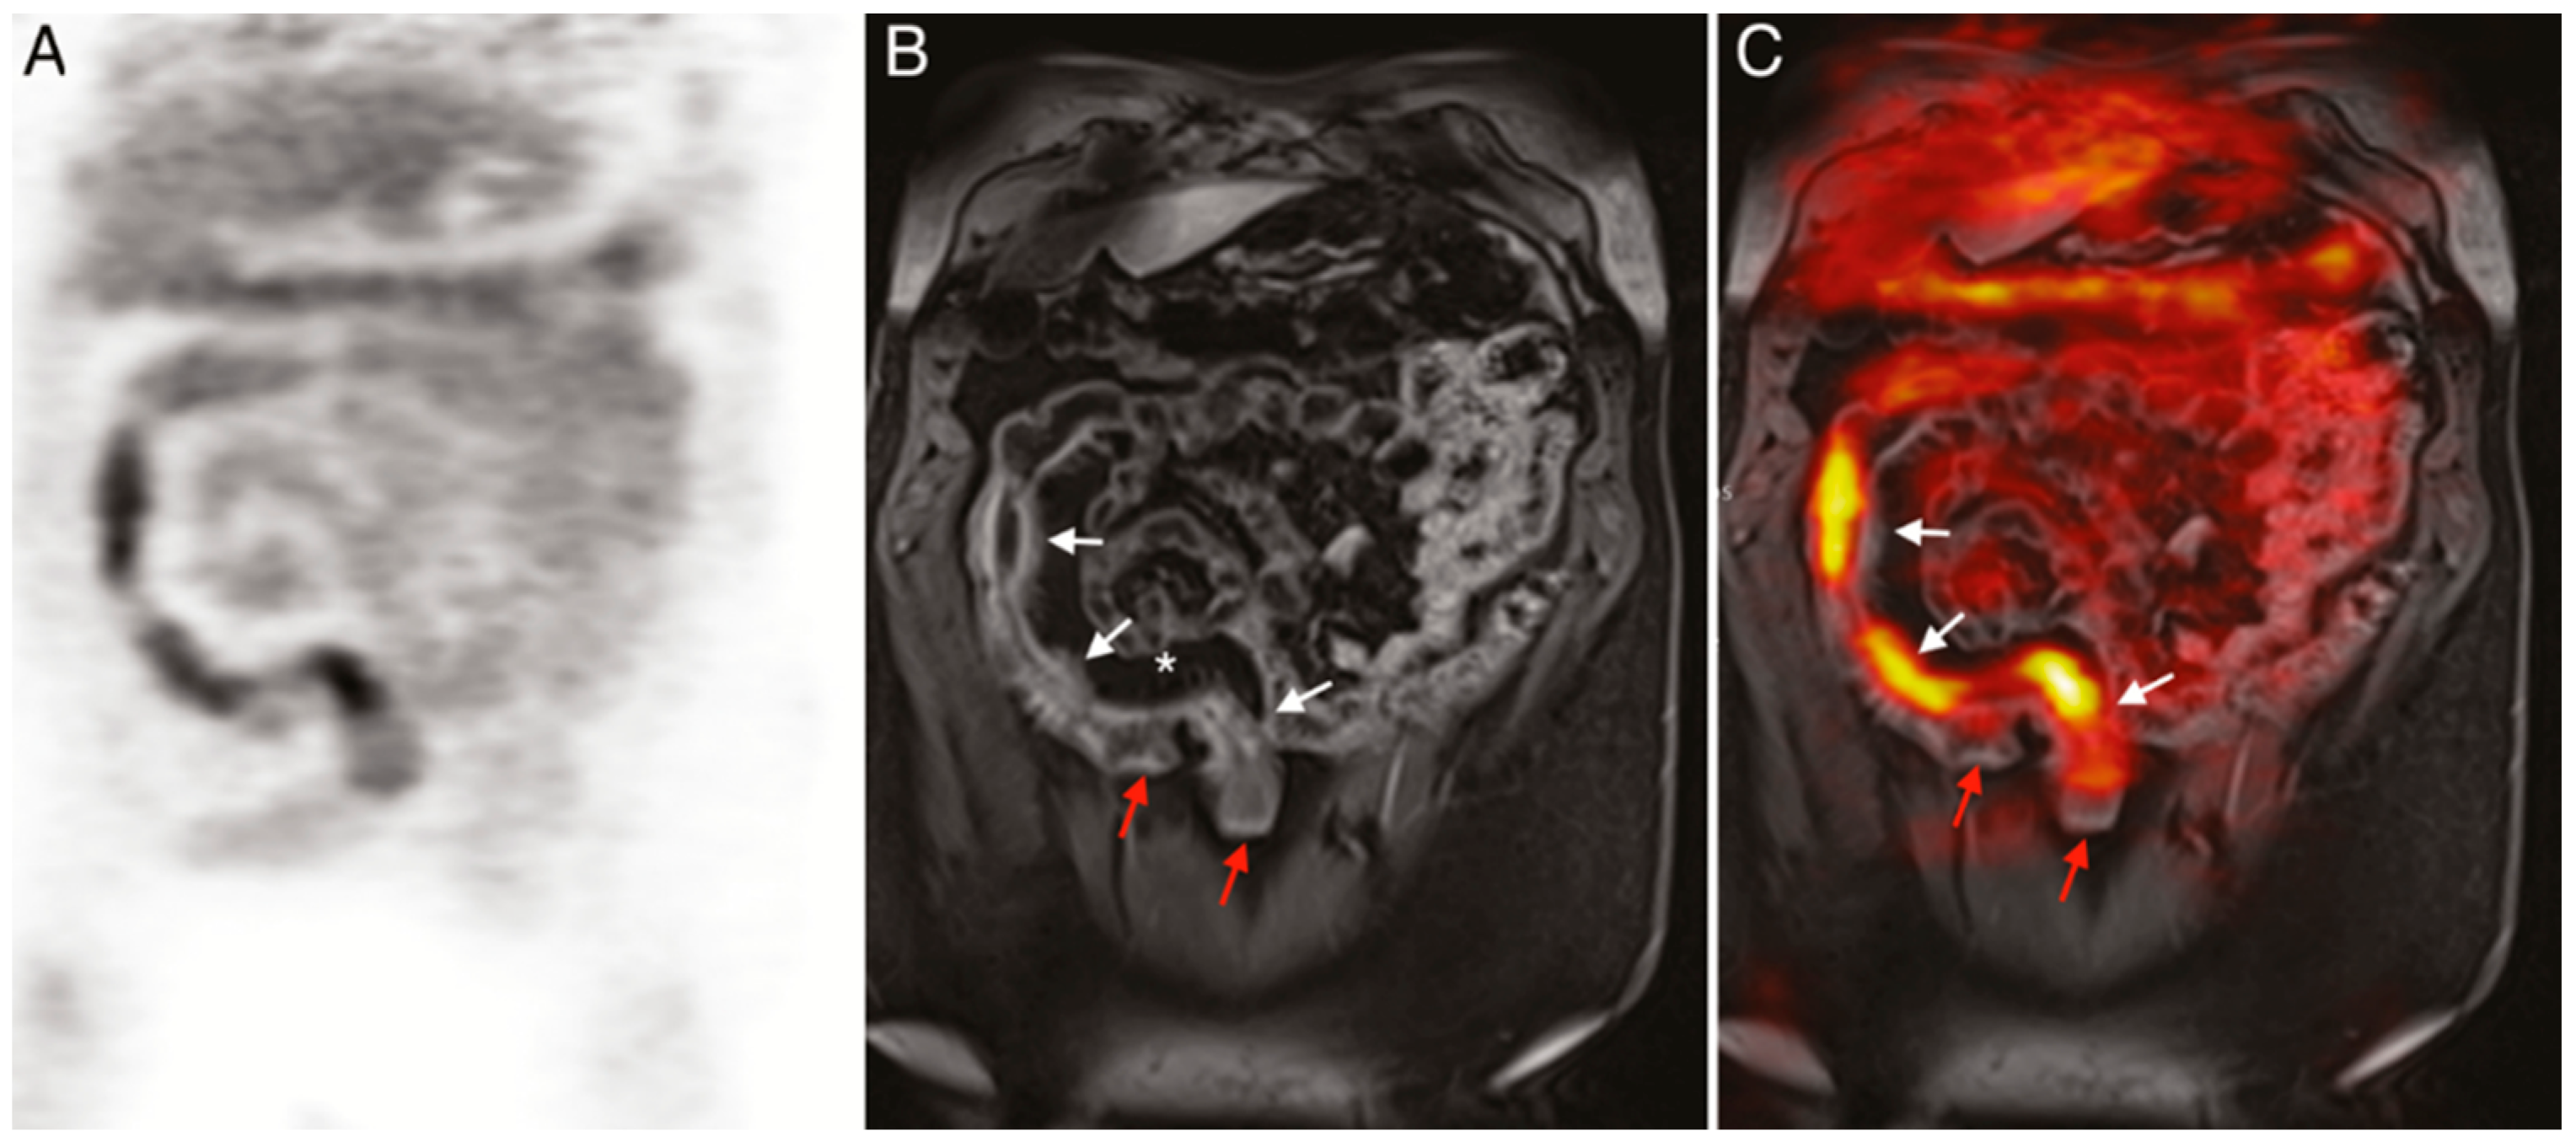

- Catalano, O.A.; Wu, V.; Mahmood, U.; Signore, A.; Vangel, M.; Soricelli, A.; Salvatore, M.; Gervais, D.; Rosen, B.R. Diagnostic Performance of PET/MR in the Evaluation of Active Inflammation in Crohn Disease. Am. J. Nucl. Med. Mol. Imaging 2018, 8, 62–69. [Google Scholar]

- Le Fur, M.; Zhou, I.Y.; Catalano, O.; Caravan, P. Toward Molecular Imaging of Intestinal Pathology. Inflamm. Bowel Dis. 2020, 26, 1470–1484. [Google Scholar] [CrossRef]

- Perlman, S.B.; Hall, B.S.; Reichelderfer, M. PET/CT Imaging of Inflammatory Bowel Disease. Semin. Nucl. Med. 2013, 43, 420–426. [Google Scholar] [CrossRef]